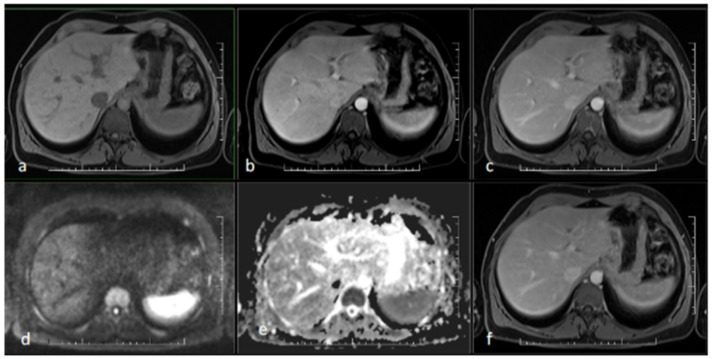

Case presentation: We report a case of early syphilis in the secondary stage, manifesting as sclerosing-cholangitis-like changes shown on ultrasonography, MR, and CT. Narrow-spectrum antibiotic therapy with procaine benzylpenicillin led to a consistent decrease in and normalization of levels of serum bilirubin and other markers of hepatic injury. Repeated sonography and MR cholangiography showed minimal residual changes in the intrahepatic biliary tree.